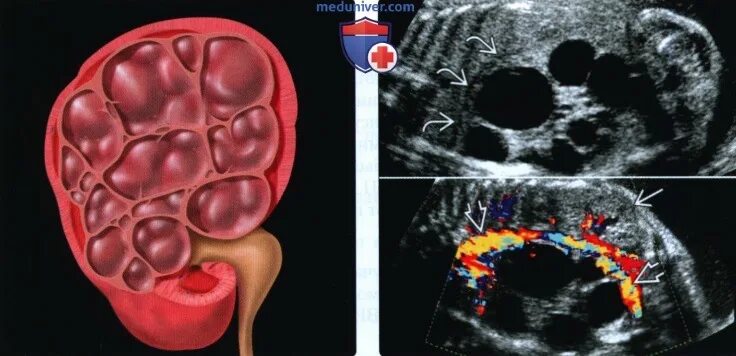

Мультикистозная почек плода